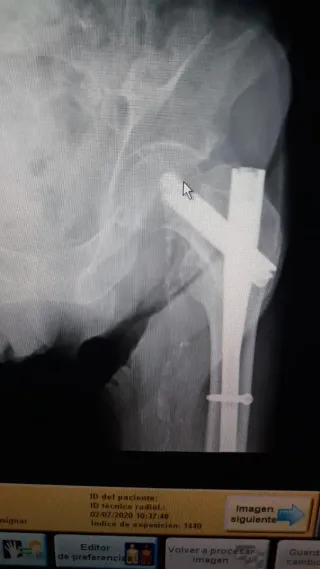

Reveladora Digital Carestream DirectView Max CR

Se vende reveladora digital Carestream DirectView Max CR, equipo de alta fiabilidad diseñado para entornos clínicos con alto volumen de trabajo. Ofrece procesamiento rápido de placas, excelente calidad de imagen y un flujo de trabajo totalmente automatizado. Características principales - Sistema CR de alto rendimiento, ideal para radiología general. - Capacidad de procesar múltiples casetes simultáneamente. - Calidad de imagen Carestream, con algoritmos avanzados de mejora. - Interfaz intuitiva y fácil integración con PACS/RIS. - Diseño robusto, pensado para uso continuo.